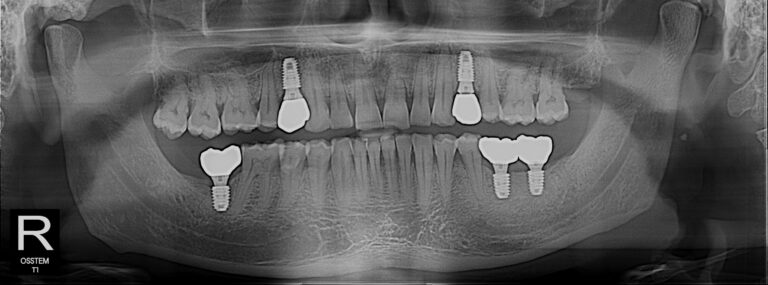

We certainly do. Our clinic is equipped with modern diagnostic technology, including Digital X-rays and CAD-CAM systems for digital restoration. We also utilize 3-D guided technology for precise implant placement.

A dental implant is a titanium post surgically placed into the jawbone to replace the root of a missing tooth. A crown is then fitted on top, giving you a natural-looking, permanent replacement. Dr. Rahman uses 3D CT-guided technology to plan and place implants with precision, minimizing risk and improving outcomes. Most adults with good general health are suitable candidates. The best way to know for sure is to book a consultation — Dr. Rahman will assess your bone density, gum health, and overall suitability during your visit.

Our clinic is equipped with modern dental technology including Digital Dental X-rays (safe, low-radiation imaging), CAD-CAM digital dental restoration (for precise, same-day crowns and restorations), 3D CT-guided dental implant planning, and the Invisalign clear aligner system. We also have strong laboratory partnerships to ensure the highest quality of prosthetic and cosmetic work.